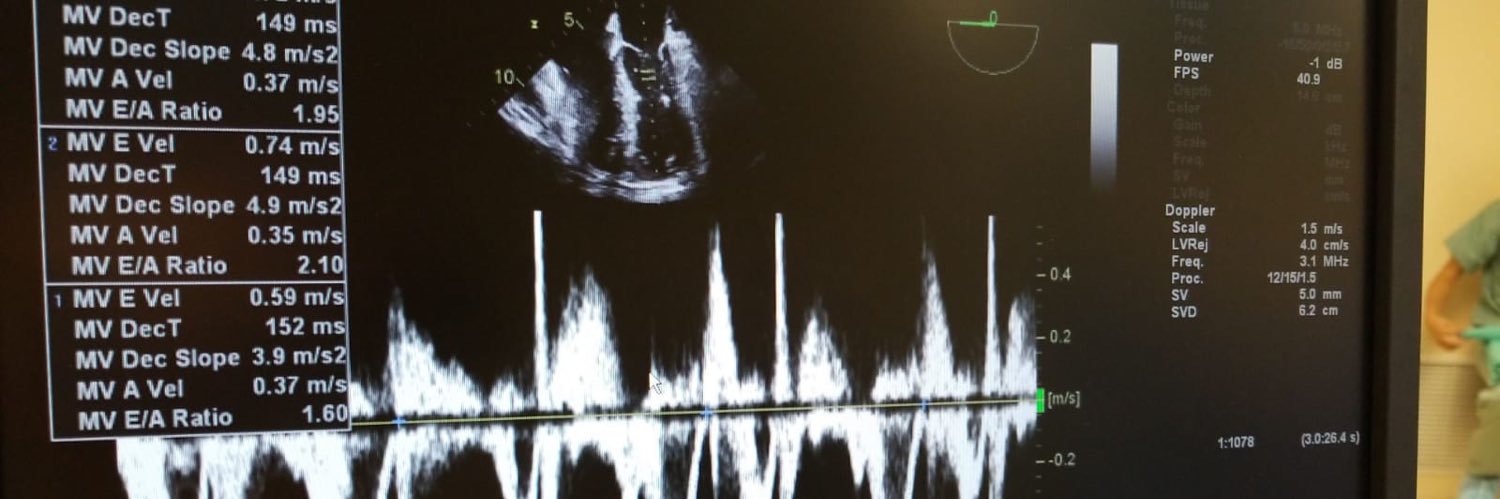

@AlisonR_MD

Cardiac anesthesiologist with an interest in music, cycling, yoga and the outdoors.